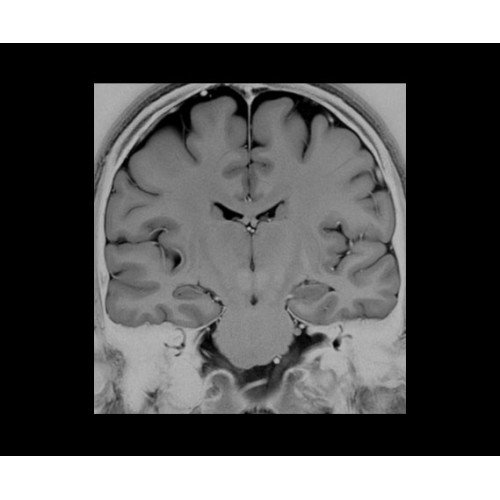

В системе SIGNA PET/MR есть все инструменты, необходимые для выявления маркеров разных заболеваний и для создания новых протоколов. ПЭТ/МРТ можно использовать совместно с мультиядерной спектроскопией в лаборатории in vivo для изучения быстрых биохимических процессов. Кроме того, PET ToolBox и набор инструментов Orchestra предоставляют персональный доступ к функциям реконструкции изображений для ПЭТ и МРТ, ускоряя и упрощая работу с необработанными данными.

• Специальный пакет приложений для измерения и сравнения объемных изображений ЦНС с нормами поможет вам в диагностике нейродегенеративных заболеваний, а дополнительные инструменты визуализации — в постановке точного диагноза с помощью бета-амилоидов и радиоизотопных маркеров ФДГ.

• In vivo лаборатория — получайте полные данные биохимических процессов in vivo с мультиядерной спектроскопией на SIGNA PET/MR.